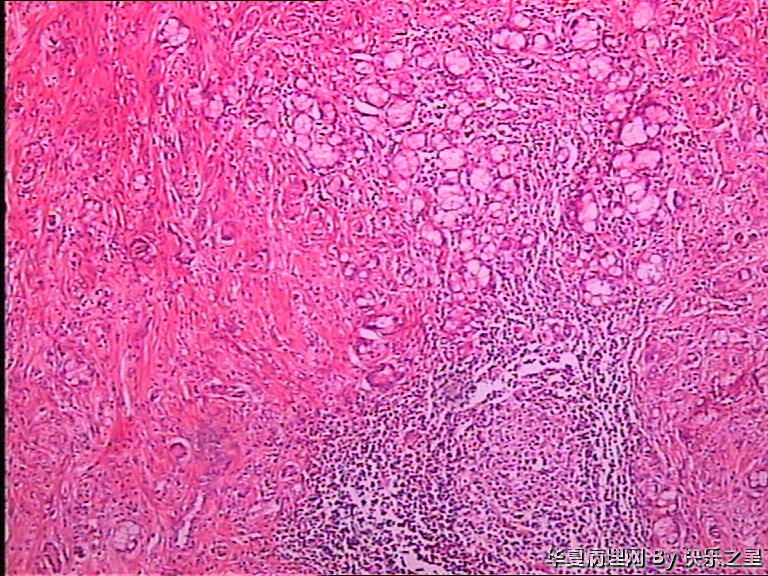

阑尾杯状细胞腺类癌?

• 阑尾杯状细胞腺类癌?图3

图3

类癌,像的,期待酶标结果~~~

能想到杯状细胞类癌就很不错了!是不是类癌或腺类癌就得看免疫组化了。不怕做不到,就怕想不到。

首选转移性阑尾杯状细胞类癌鉴别印戒细胞癌

杯状细胞类癌,应该没有 问题。